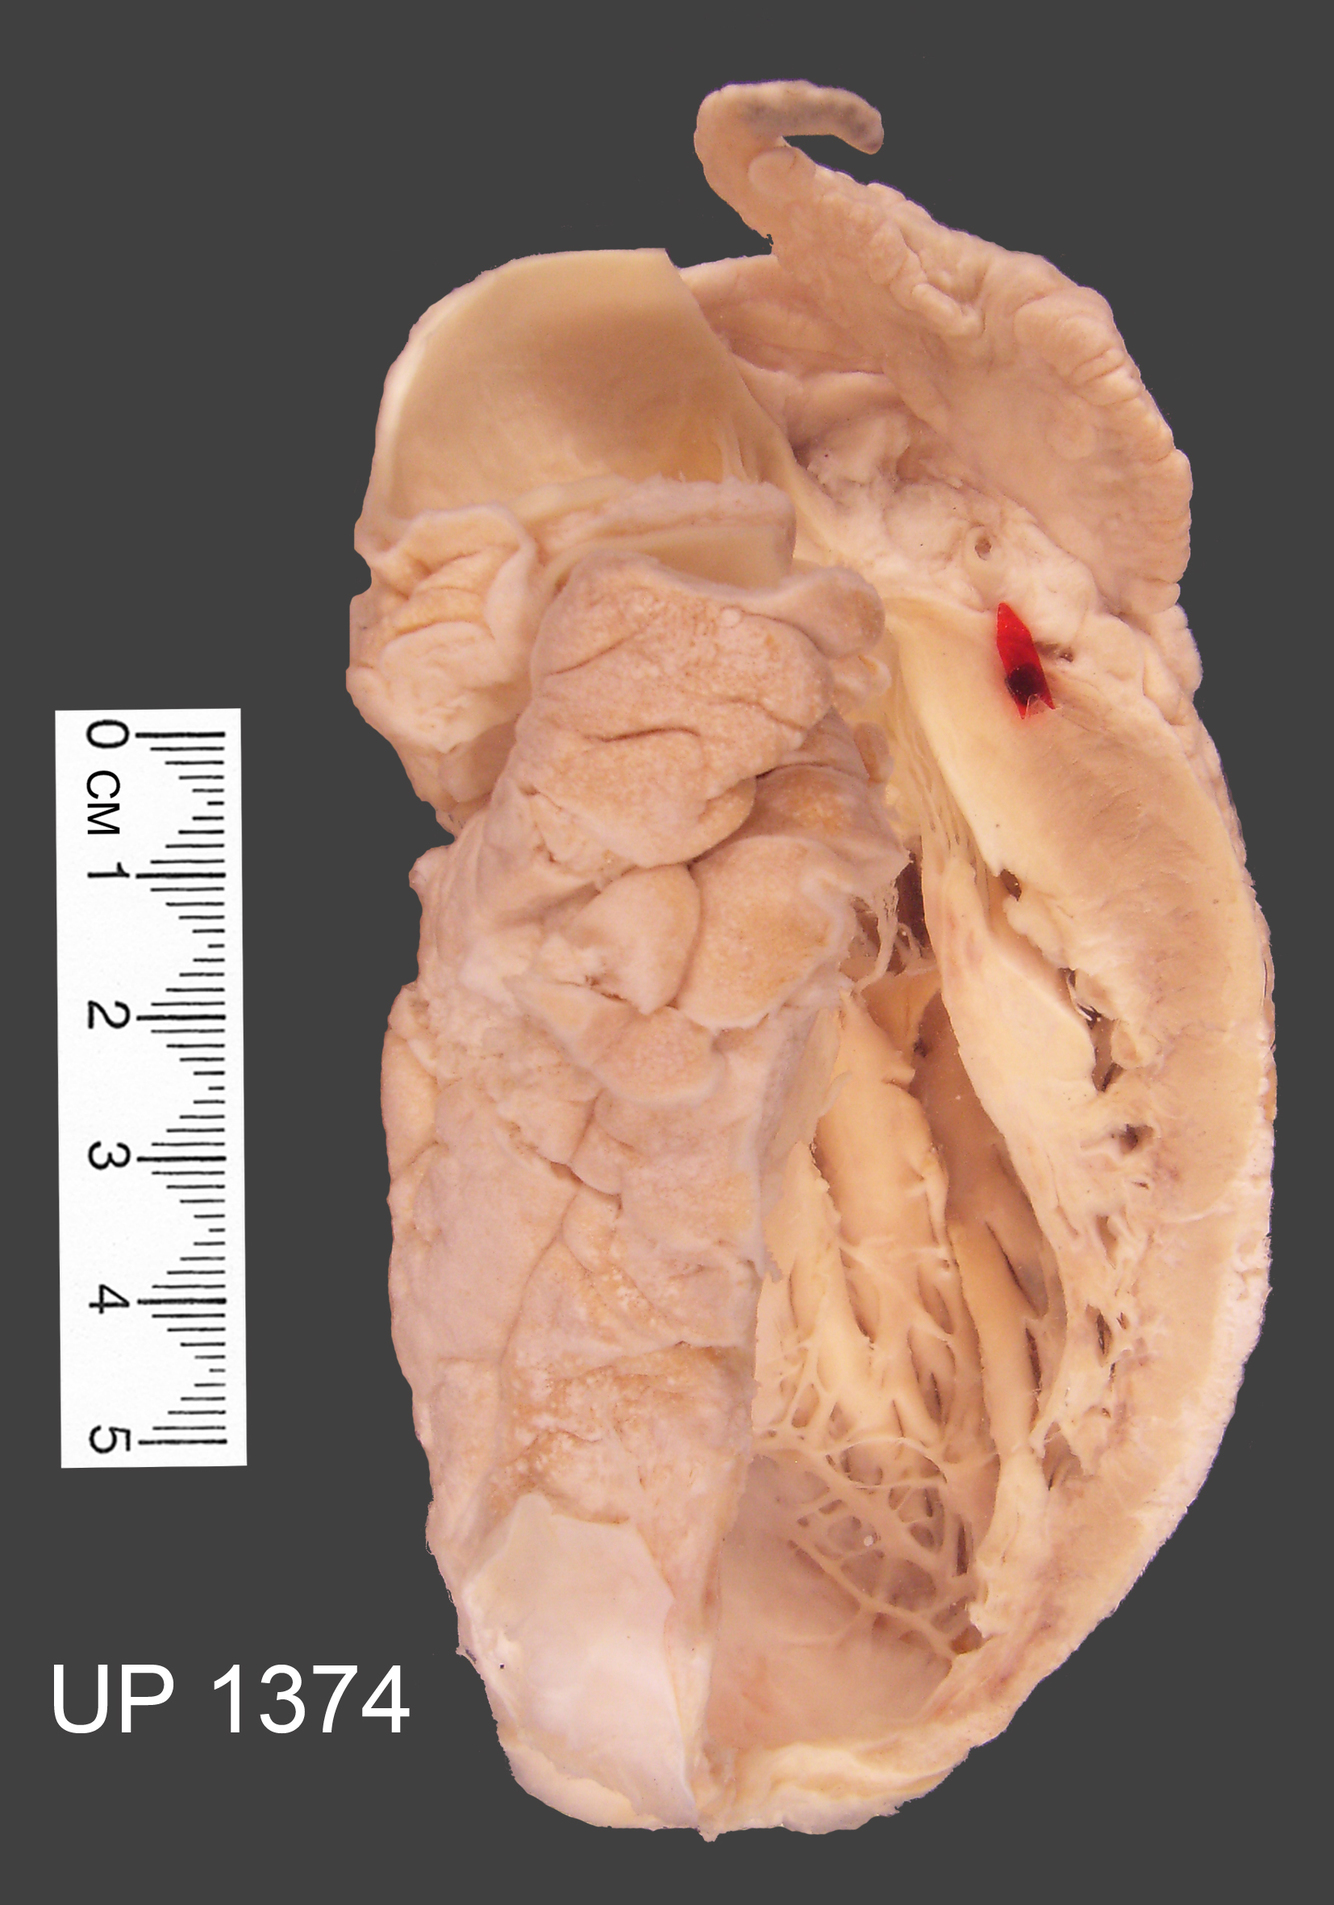

The mounted specimen of his heart has been bisected longitudinally and an arrow points to rupture of the myocardium over the infarct.

Ventricular rupture is a complication of myocardial infarction. It occurs in 1-2% of transmural infarcts usually in the first 4-5 days.

On the cut surface the recent haemorrhagic infarct can be seen in the posterolateral wall of the left ventricle.

There is also an extensive scar resulting from the previous episodes of ischaemic necrosis of the myocardium.

The coronary arteries are narrowed by atherosclerosis.